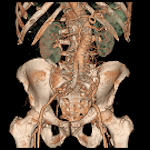

②高速な撮影 : 全身を20秒、0.625mm厚にて撮影可能